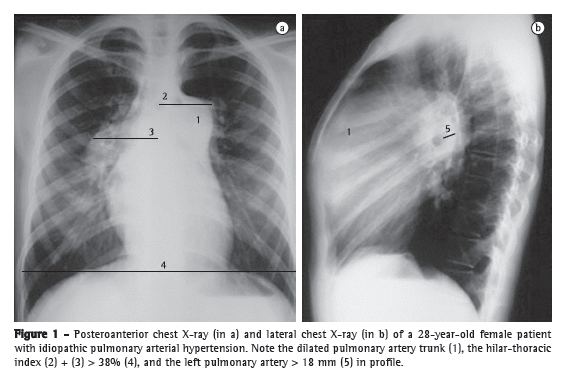

The biological properties of the chest provide a valuable opportunity for assessment with the use of EIT, because air and blood, two materials with opposite resistances, share the same compartment and vary their volumes rhythmically during the cardiorespiratory cycle. The periodic change in intrathoracic blood volume during cardiac work and the distension of pulmonary microcirculation resulting from the blood flow through the pulmonary vessels are associated with the cyclic change in the electrical properties of the lung parenchyma over time. The increased blood volume in the lung parenchyma results in a 1% decrease in lung electrical impedance (blood being five time less resistant than is air).

Regional changes in blood flow can be visualized by EIT in two ways. The first, which is based on the indicator dilution technique, involves the use of an electrically conducting fluid as contrast material, similarly to CT and MRI studies. The second approach analyzes the changes in the lung parenchyma impedance resulting from the change in systolic volume during the cardiac cycle, cycle by cycle. Coupling of image acquisition with the R-wave on electrocardiogram (the ECG-gated technique) filters ventilation-related fluctuations, obtaining only those that are due to circulation. The resulting image is likely to reflect pulmonary circulation pulsatility or distensibility.

An excellent model of disease in the pulmonary microcirculation is PAH, in which vascular remodeling directly affects the distensibility properties of microcirculation. When vascular compliance is reduced, with consequent accommodation of lower volumes, the electrical impedance change in PH is likely to be decreased as well. In one study,(59) EIT was used in patients with PH for determining vascular response to vasodilator testing with epoprostenol during invasive hemodynamic assessment. Of the 8 patients evaluated, 7 did not meet the vasodilator response criteria, EIT showing no impedance change in those 7. In the lone responder, the increase in impedance change was found to correlate strongly with decreases in mPAP and pulmonary vascular resistance, regardless of the increase in systolic volume. In another study,(60) the differences in the impedance of the pulmonary circulation were analyzed in 21 patients with idiopathic PAH (IPAH) and 30 healthy subjects. The authors observed a reduction in impedance change in the IPAH group, which provides support for the use of EIT in the assessment of the pulmonary circulation and of PH.

In Brazil, a 32-electrode EIT scanner is being developed for the assessment of lung perfusion. In the context of IPAH, the images obtained with this new scanner (Figure 8) are encouraging, demonstrating not only a reduction in electrical impedance, as in the two aforementioned studies, but also a change in the impedance wave morphology, which might correlate with the pulse wave of the pulmonary circulation.